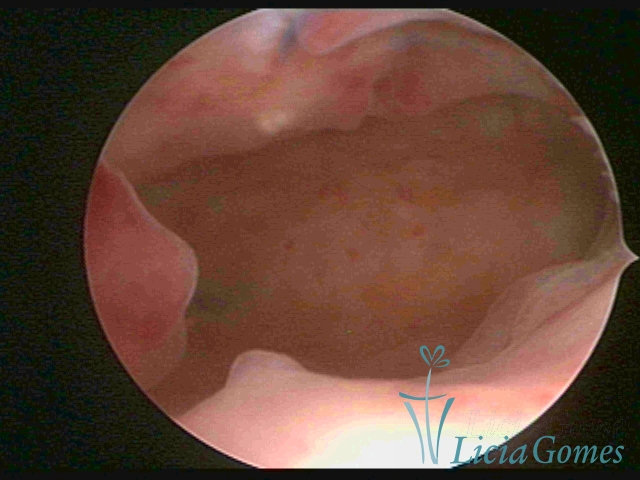

Na hipertrofia simples há um aumento da espessura endometrial com protuberância do pontilhado glandular, diferindo do padrão endometrial proliferativo pela perda da vascularização reticular superficial. Outra forma de hiperplasia simples é a glandular cística, onde também se visualiza lesões císticas intercaladas ao endométrio hipertrófico.